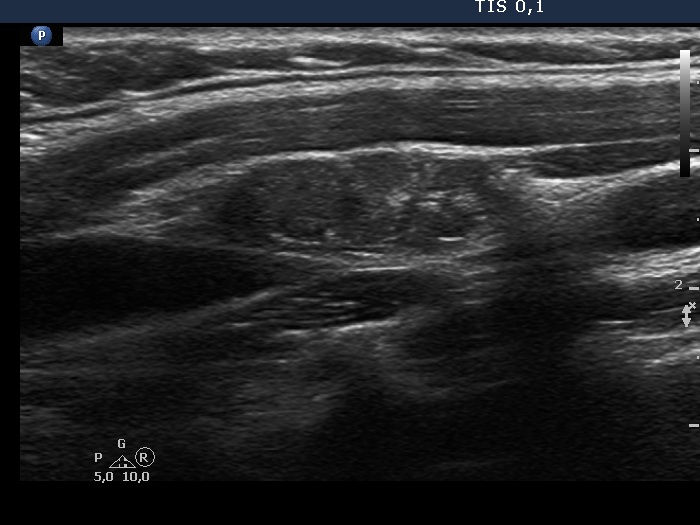

Ultrasonography. The thyroid was echonormal. There were two nodules in the left lobe. The upper lesion was a dominantly isoechoic nodule which had microcalcifications while the lower one was a hypoechoic nodule. There were numerous microcalcification relatively far from the primary tumor focus. The upper nodule was avascular while the lower one presented both intranodular and perinodular blood flow.

A conglomerate of lymph nodes was found 2 cm above the left lobe. The nodes did not have hilum but contained microcalcifications and presented irregular vascular pattern. (This was not noticed on the previous ultrasound examination.)